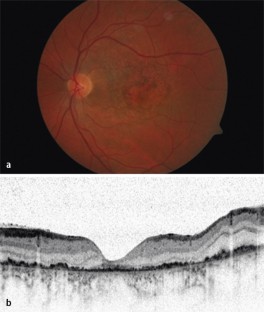

Abb. 1

Abb. 2

Abb. 3

Abb. 4

Abb. 5

Abb. 6

Bezüglich der optimalen Therapie des traumatischen Makulaforamens (TMF) gibt es keine Einigkeit. Wir berichten über den Spontanverschluss von TMF in 2 Fällen. Beim 1. Patienten führte der Verschluss zu einem Visusanstieg von 0,2 auf 0,8. Der 2. Patient zeigte trotz des Verschlusses wenige Tage nach dem Trauma keinen Visusanstieg. Dies ist vermutlich auf eine irreversible Schädigung von Photorezeptoren und retinalem Pigmentepithel zurückzuführen. Wegen der nicht seltenen Möglichkeit eines Spontanverschlusses von TMF hat eine abwartende Haltung bei diesem Krankheitsbild ihre Berechtigung.

The optimal treatment approach for traumatic macular holes (TMH) is still controversial. We report two cases of spontaneous closure of TMH. In the first patient, closure resulted in an increase in visual acuity from 0.2 to 0.8. In the second case, no increase in visual acuity was detectable despite spontaneous closure of the TMH within a few days after the trauma. This may be explained by an irreversible damage of the photoreceptors and retinal pigment epithelium. In patients with TMH, a waiting approach should be considered because of the possibility of spontaneous closure of TMHs.